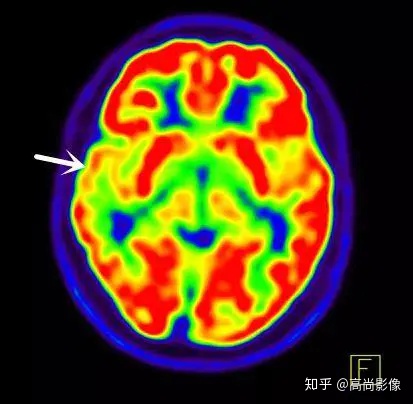

發(fā)作間期癲癇灶呈代謝減低

發(fā)作期癲癇灶呈代謝增高